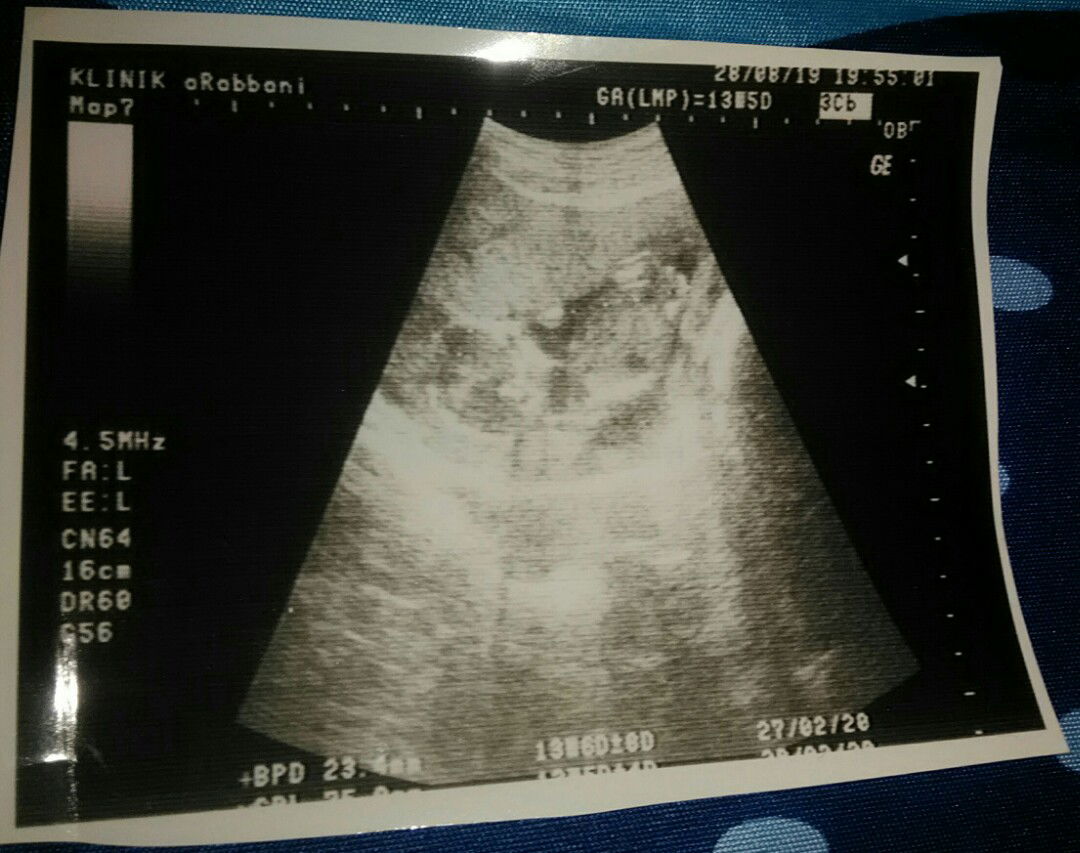

cara melihat berat dan uk panjang janin di hasil usg

Halo mums... Mums saya habis usg ,saya mau nanya untuk melihat berat badan janin dan ukuran panjang janin yg mana ya ? Saya gak ngerti cara baca usg gimana ?mohon pencerahannya mum ... Terima kasih mums